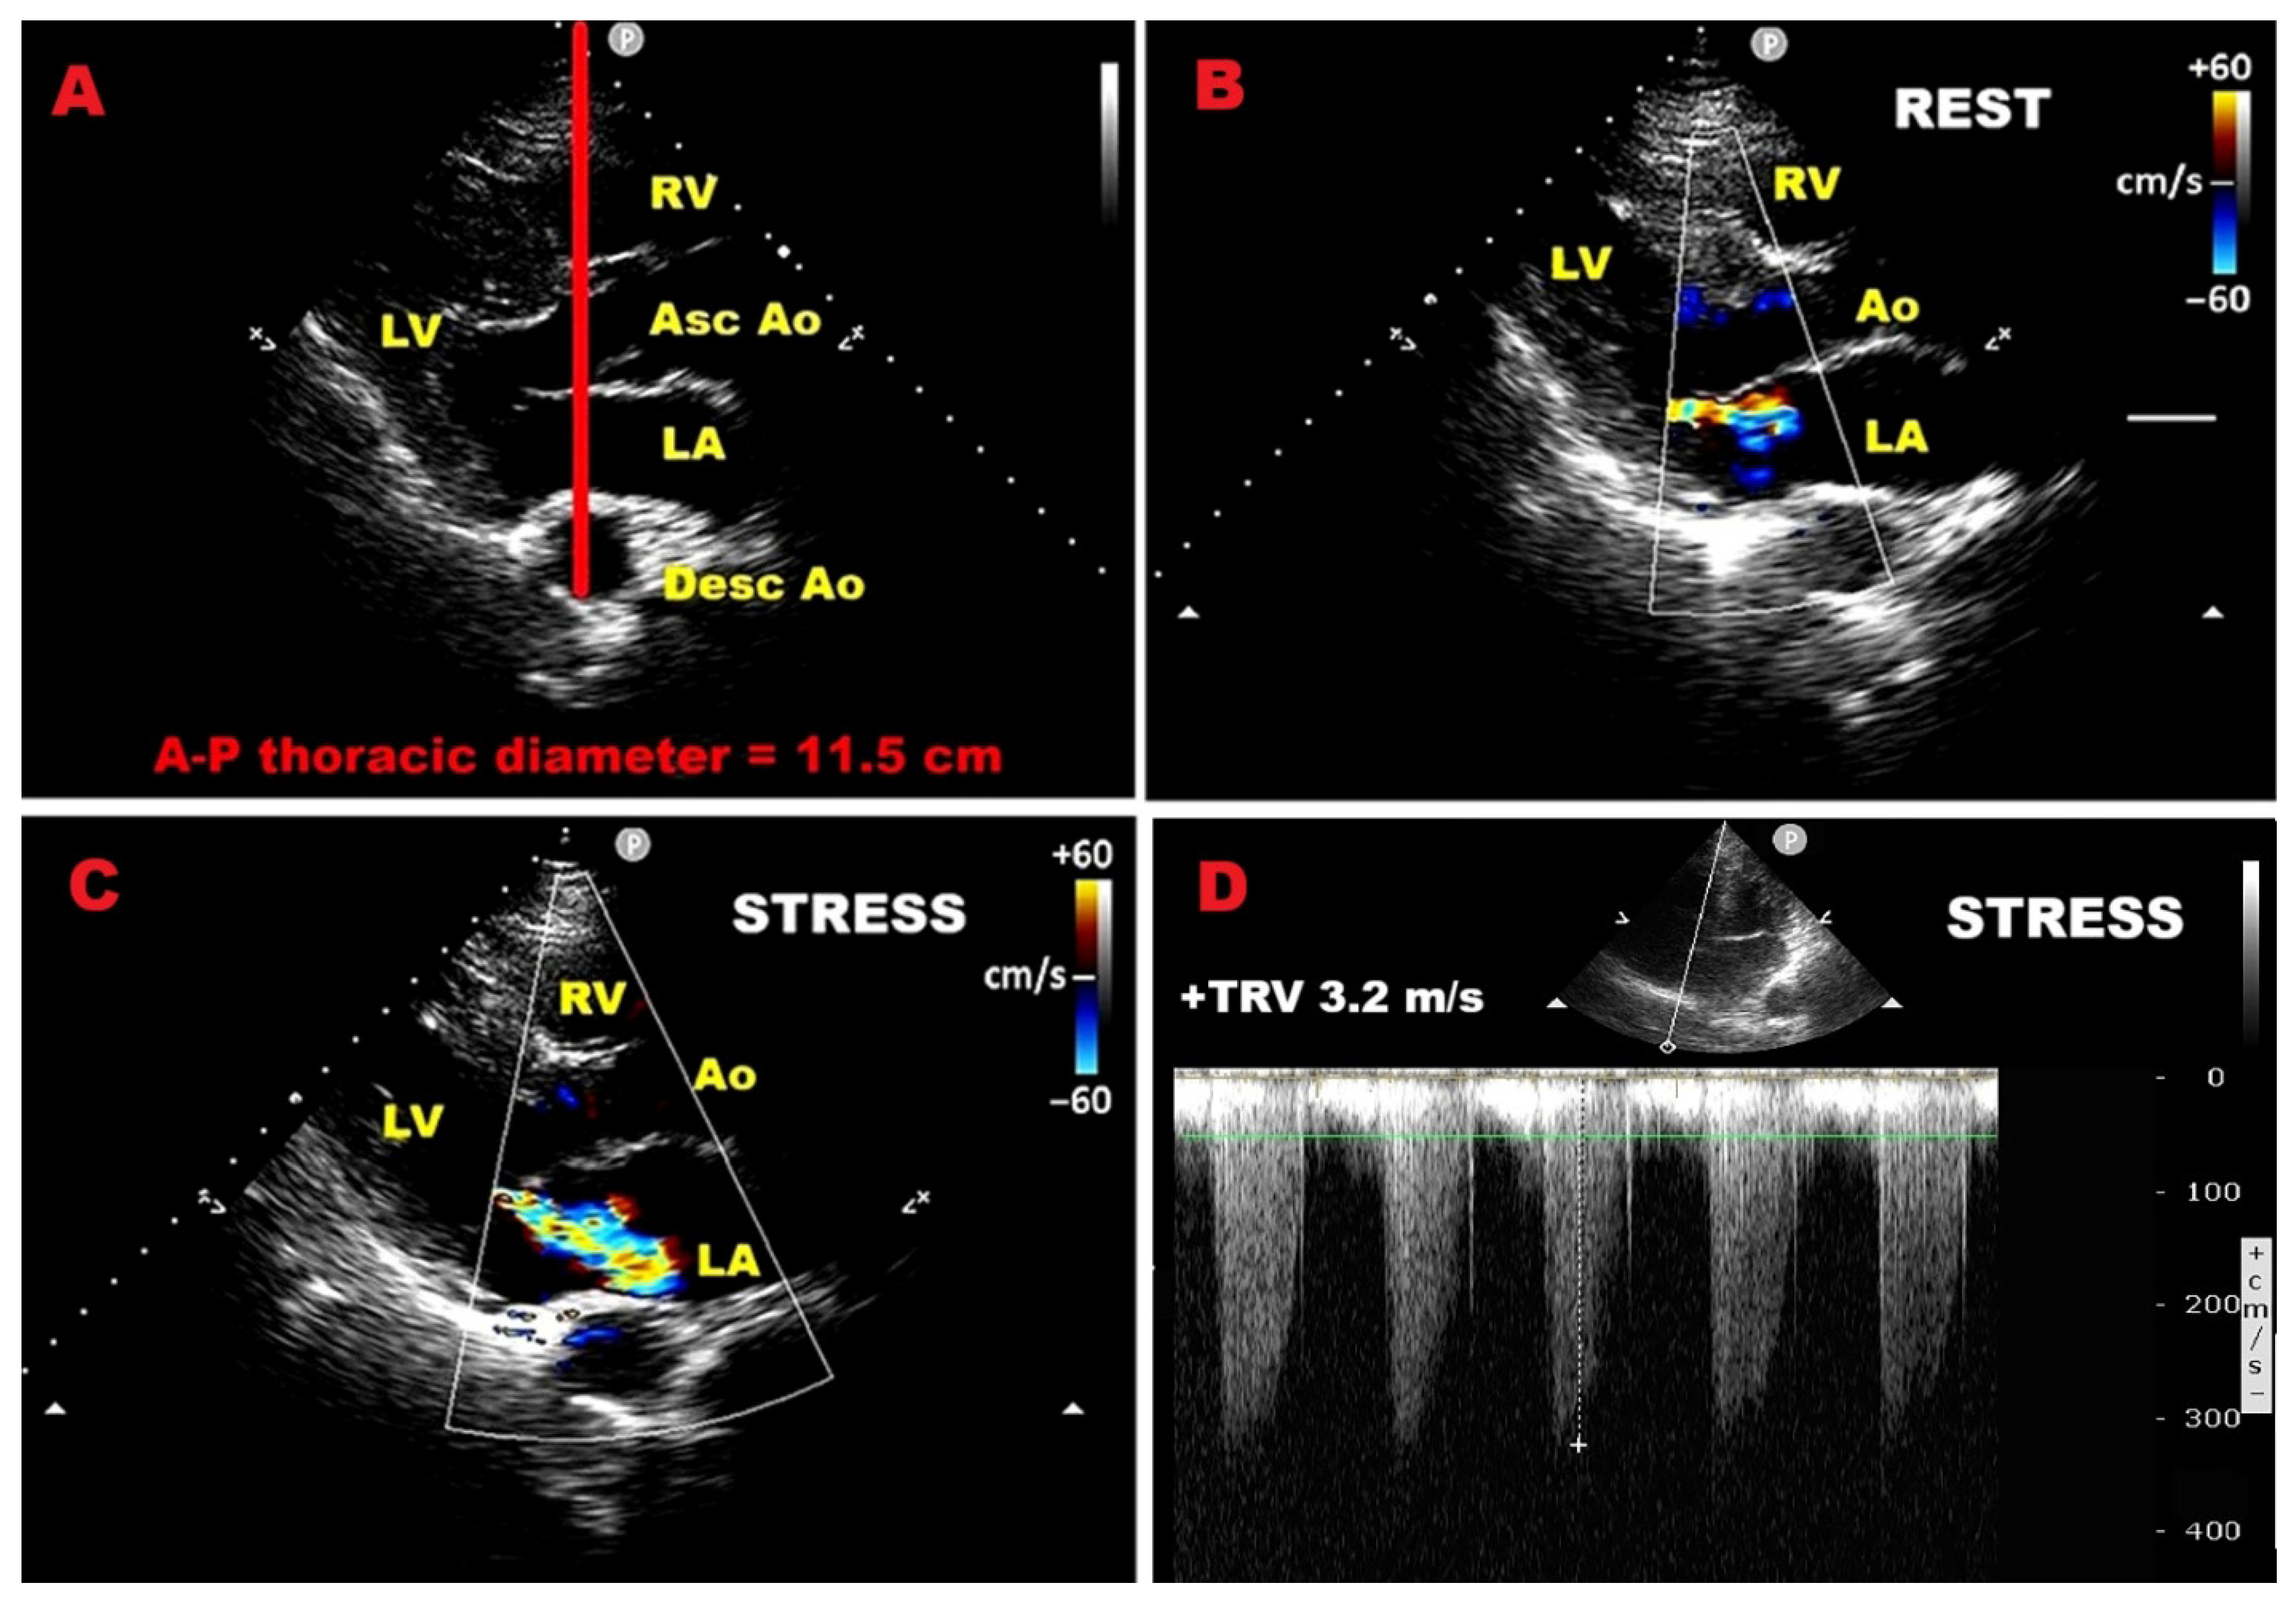

4. Prognostic Indicators Assessed Using Exercise Stress Echocardiography

9.4. Influence of Chest Wall Conformation on ESE Results

3.7. Pulmonary Hypertension